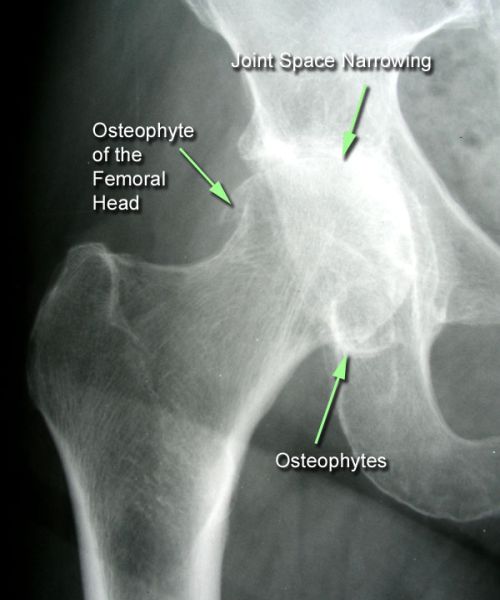

Αποτελεί μια εκφυλιστικού τύπου αρθρίτιδα της άρθρωσης του ισχίου. Με την πάροδο του χρόνου προκαλείται παραμόρφωση της αρθρικής επιφάνειας τόσο στην κεφαλή του μηριαίου όσο και στην κοτύλη.

Εμφανίζεται συχνότερα σε γυναίκες προχωρημένης ηλικίας ενώ υπάρχει και γενετικό υπόβαθρο προδιάθεσης. Παρουσιάζει αυξημένη συχνότητα εμφάνισης σε ασθενείς με συγγενή δυσπλασία ισχίου, ιστορικό αγγειακού τραυματισμού της κεφαλής του μηριαίου, επαγγελματίες αθλητές καθώς και σε άτομα με επαγγέλματα που σχετίζονται με άρση βάρους και έντονη μυϊκή καταπόνηση.

Η κλινική εξέταση αναδεικνύει άλγος στην περιοχή του ισχίου κατά τις κινήσεις της άρθρωσης, χωλότητα βάδισης λόγω άλγους, μείωση της έκτασης - κάμψης και έσω στροφής του ισχίου. Η επιβεβαίωση της διάγνωσης γίνεται με απλή ακτινογραφία.